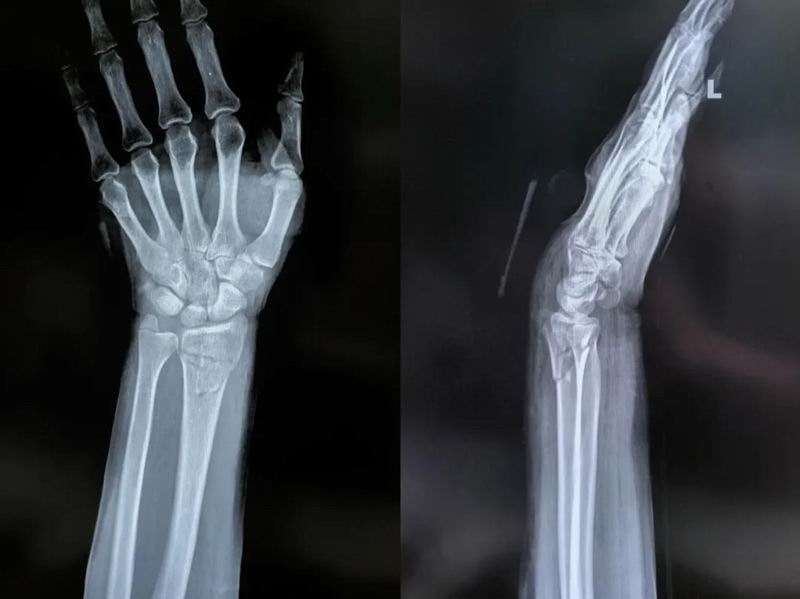

640_wx_fmt=png&from=appmsg&tp=webp&wxfrom=5&wx_lazy=1 (13)

患者手法复位后

桡骨远端骨折手法复位术是一门融合了医学知识和手工技巧的“艺术”,经验丰富的骨科医生往往能在几分钟内完成这一“神奇”的复位过程。对于患者而言,了解这一过程有助于缓解治疗焦虑,更好地配合医生完成治疗和康复。成功的治疗不仅依赖于医生的技术,也需要患者的坚持和耐心。